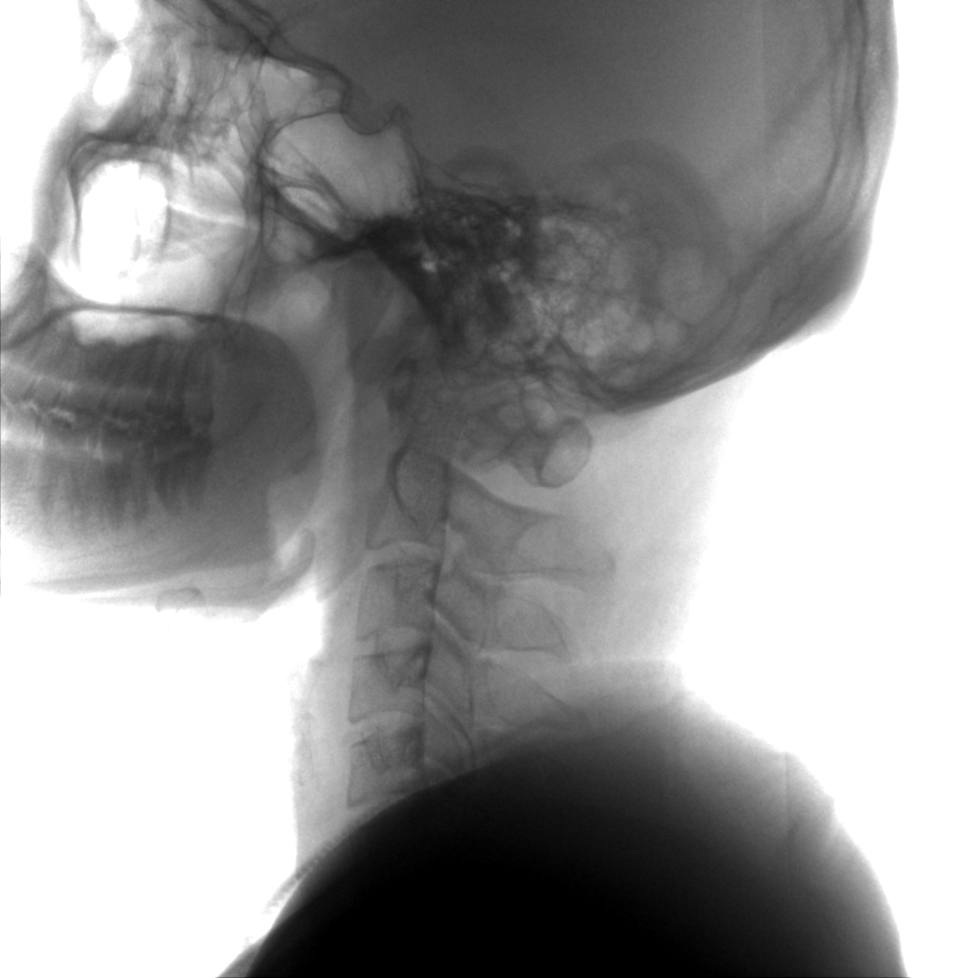

術中三維成像和橫斷面圖像提供多角度的手術診斷信息,輔助醫生進行術中評估判斷,諸如骨折復位情況和內植入螺釘的尺寸和位置,輔助手術更好地完成。

提供更大的術中三維成像視野,采集更多圖像信息,可一次拍全全段頸椎、全段腰椎、七節胸椎、雙側骶髂關節、股骨頭及單側盆骨。